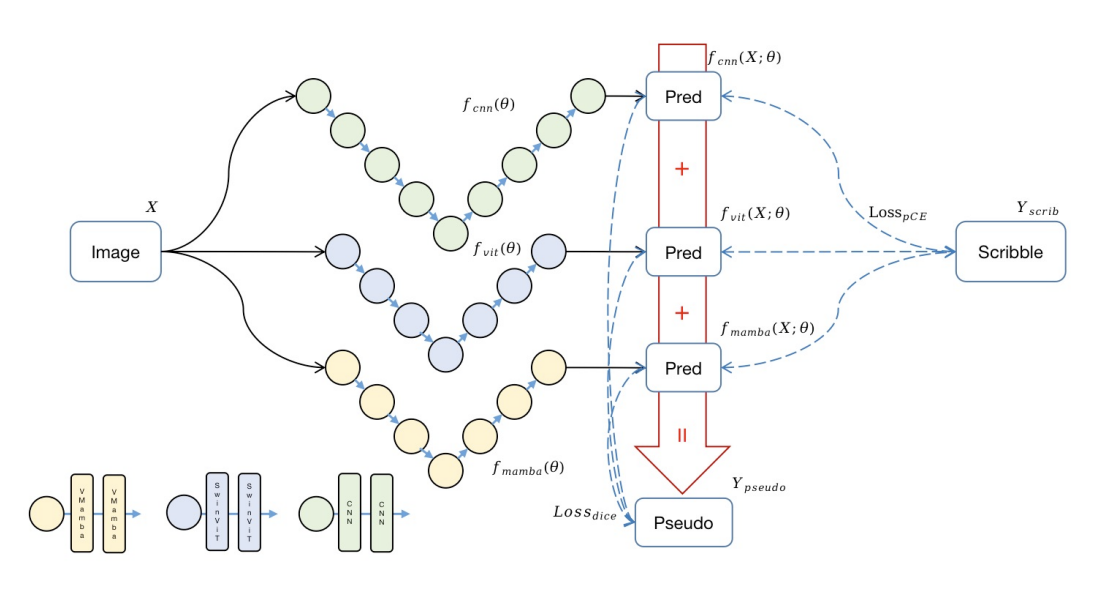

Semi-Mamba-UNet: The Framework of Contrastive Cross-Supervised Visual Mamba-based UNet for Semi-Supervised Medical Image Segmentation.

论文提出的Weak - Mamba - UNet是一种用于基于涂鸦的医学图像分割的弱监督学习框架,结合了Mamba、CNN 和 Vision Transformer(ViT)的优势。

该方法构建了三个具有相同对称编码器 - 解码器结构的网络:基于 CNN 的 UNet 用于提取详细的局部特征,基于Swin Transformer的SwinUNet用于理解全局上下文信息,基于Visual Mamba的Mamba - UNet用于高效建模长程依赖关系。

通过使用伪标签的协作和交叉监督机制,在有限监督信号的条件下,实现三个网络之间的迭代学习和优化,最小化由基于涂鸦的部分交叉熵损失和密集信号伪标签骰子系数损失组成的总损失,以提升分割性能。

创新应用Mamba架构:首次将基于Mamba的分割网络应用于基于涂鸦注释的医学图像分割的弱监督学习中,利用Mamba在捕捉长程依赖方面的优势,提升医学图像分割效果。

多架构协同学习:提出新颖的多视图交叉监督框架,使CNN、ViT和Mamba三种不同架构在有限监督信号下协同工作。通过随机生成权重因子融合三个网络的预测结果得到伪标签,增强了伪标签的多样性和模型的鲁棒性、泛化性。

性能优势明显:在公开的MRI心脏分割数据集上进行实验,Weak - Mamba - UNet在多种评估指标上优于仅使用UNet或SwinUNet的类似弱监督学习框架,证明了该框架能有效整合不同类型算法的优势,提升网络分割性能 。